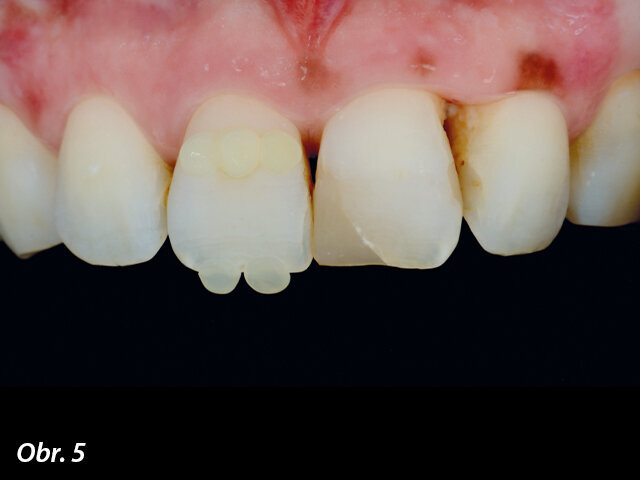

Výběr odstínu pomocí tzv. kompozitní „knoflíkové“ techniky (Composite Button Technique), s (4) a bez (5) polarizačních filtrů.